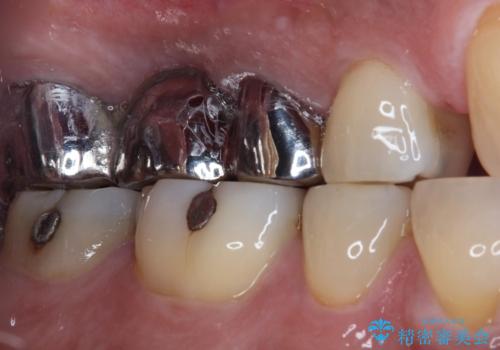

- 奥歯のブリッジに違和感があるとのことで来院された患者様です。

土台となっている最後方の歯に痛みがあるようで、むし歯処置あるいは根管治療を行う前提で金属ブリッジを除去することとしました。

銀歯に隠れていて術前のレントゲンでははっきりと分かりませんでしたが、元々非常に大きなむし歯があったようで、銀歯の中で神経組織が壊死を起こしていました。

速やかに根管治療を行い、無事に痛みを取り除くことができました。